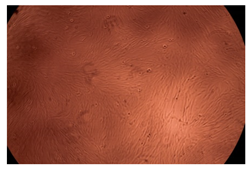

The results of the cytotoxicity assay, given in Figure 5, indicate that the tested PMs at all three established concentrations (10, 50, and 100 µg/mL) did not show cytotoxic effects on fibroblast cells at either 24 or 48 h after incubation. The percentages of cell viability were high, over 90%, in cells that were exposed to a concentration of 10 µg/mL for 24 h for all tested materials. Even at 48 h after incubation, the percentage of cell viability was as high as 90.4% in cells exposed to a concentration of 10 µg/mL for the Cop B sample. For both drug-loaded PMs, the cell viability decreased slightly at all tested concentrations. It also appears that the Dorzolamide-loaded PMs have slightly lower cell viability as compared to IMC-loaded PMs. Micrographs of the fibroblast cells after incubation times of 24 and 48 h are provided in Table 2.

Table 2.

Micrographs of fibroblast cells after 24 and 48 h incubation times, respectively.

As the cell viability values are all over 80%, the results indicate that the PMs, at the established concentrations, can be used successfully for in vivo biomedical applications.